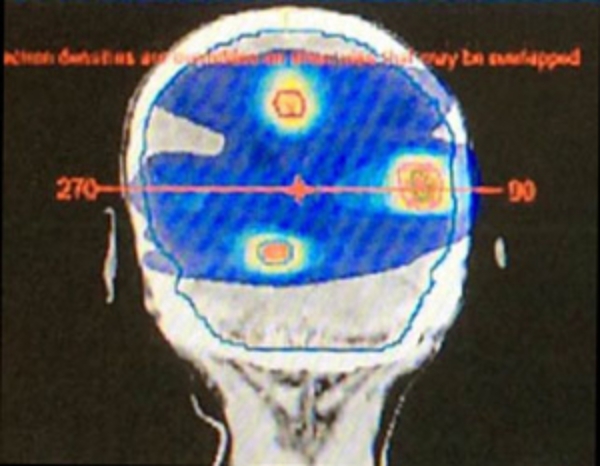

全脳照射の既往のある例

脳転移同時3個照射